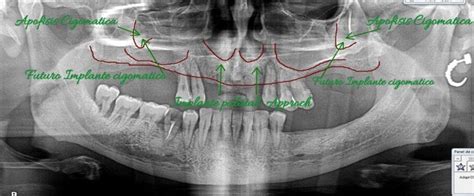

Cuando el defecto del maxilar superior es muy pronunciado existiendo una compresión severa, es necesario realizar en primer lugar un procedimiento de expansión del paladar (SARPE), para corregir el problema transversal y posteriormente corregir el problema anteroposterior con una cirugía ortognática.